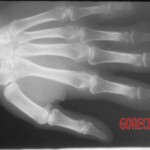

The man suffered injuries during which he lost the skin on four fingers of his left hand. It is alleged that this happened while working with soldering cylinders in the factory. Doctors decided to use a method called “degloving”. This involves taking skin from another part of the patient’s body where it is less needed and transferring it to the injured part. Usually an unsightly scar is left where the skin is removed.